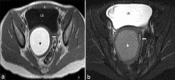

We present here a case of an uncommon complex uterine anomaly - Obstructed HemiVagina with Ipsilateral Renal Agenesis (OHVIRA), also known as Herlyn-Werner-Wunderlich syndrome in a 14-year-old girl along with sonographic (trans-abdominal and trans labial), and MRI findings. The patient underwent surgery wherein imaging findings were confirmed. An MRI has proved to be of great help in correct diagnosis avoiding surgical interventions/ laparoscopy, which were needed in past to diagnose this rare anomaly. We also discuss the development of this anomaly with the help of a relatively new theory of uro-genital development by Acien and review the literature.